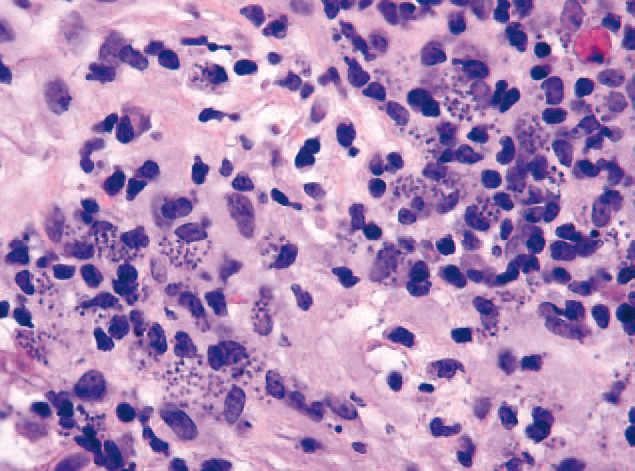

En el estudio histopatológico, además de un denso infiltrado inflamatorio constituido por linfocitos, células plasmáticas y algunos eosinófilos, se apreciaron macrófagos parasitados por microorganismos basófilos ovales de uretoplasto excéntrico y carentes de cápsula (fig. 2).

Figura 2. Múltiples macrófagos parasitados por amastigotes. (Hematoxilina-eosina, ×40.)